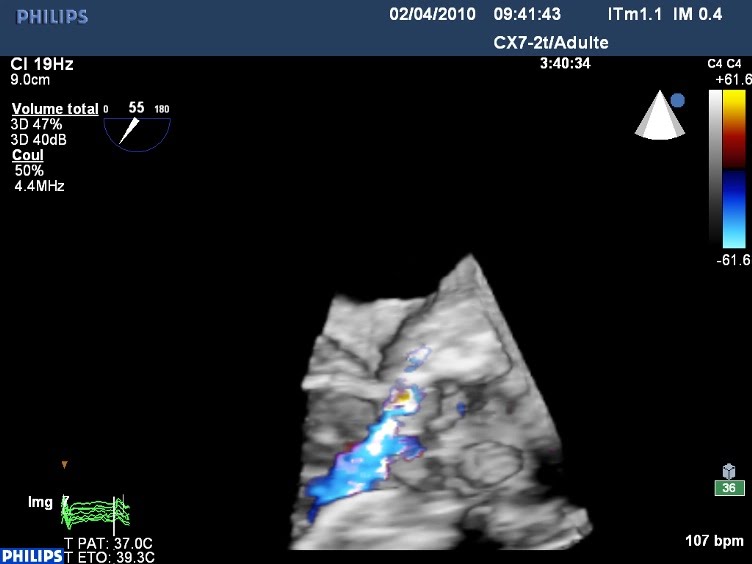

Abcès de l’anneau sur Bioprothèse à armature

Patient adressé pour suspicion d’endocardite, hémocultures postives à staph et BAV1 d’apparition récente. Abcès postérieur de l’anneau (totalement raté à l’ETT…), avec logette expansive et IA para-prothétique au sein de l’abcès. Sur l’image 3d, on visualise la logette expansive à la jonction aorto-mitrale. Les coupes en 9 écrans sont obtenues à partie de l’acquisition en ETO 3D, avec la fonction « i-slice », qui permet de découper un volume en « tranches » avec l’orientation que l’on souhaite. C’est, à mon sens, un des intérêts majeur du 3D. Ici, la première coupe en haut à gauche est dans l’aorte, la dernière dans la chambre de chasse du VG. On peut suivre l’abcès perforé de l’une à l’autre. La photo du bloc confirme les données échographiques.